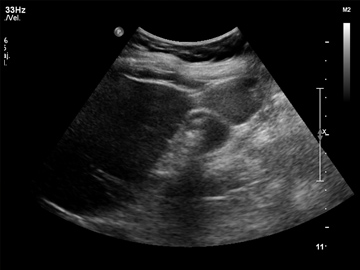

ECO Sonograma de abdomen